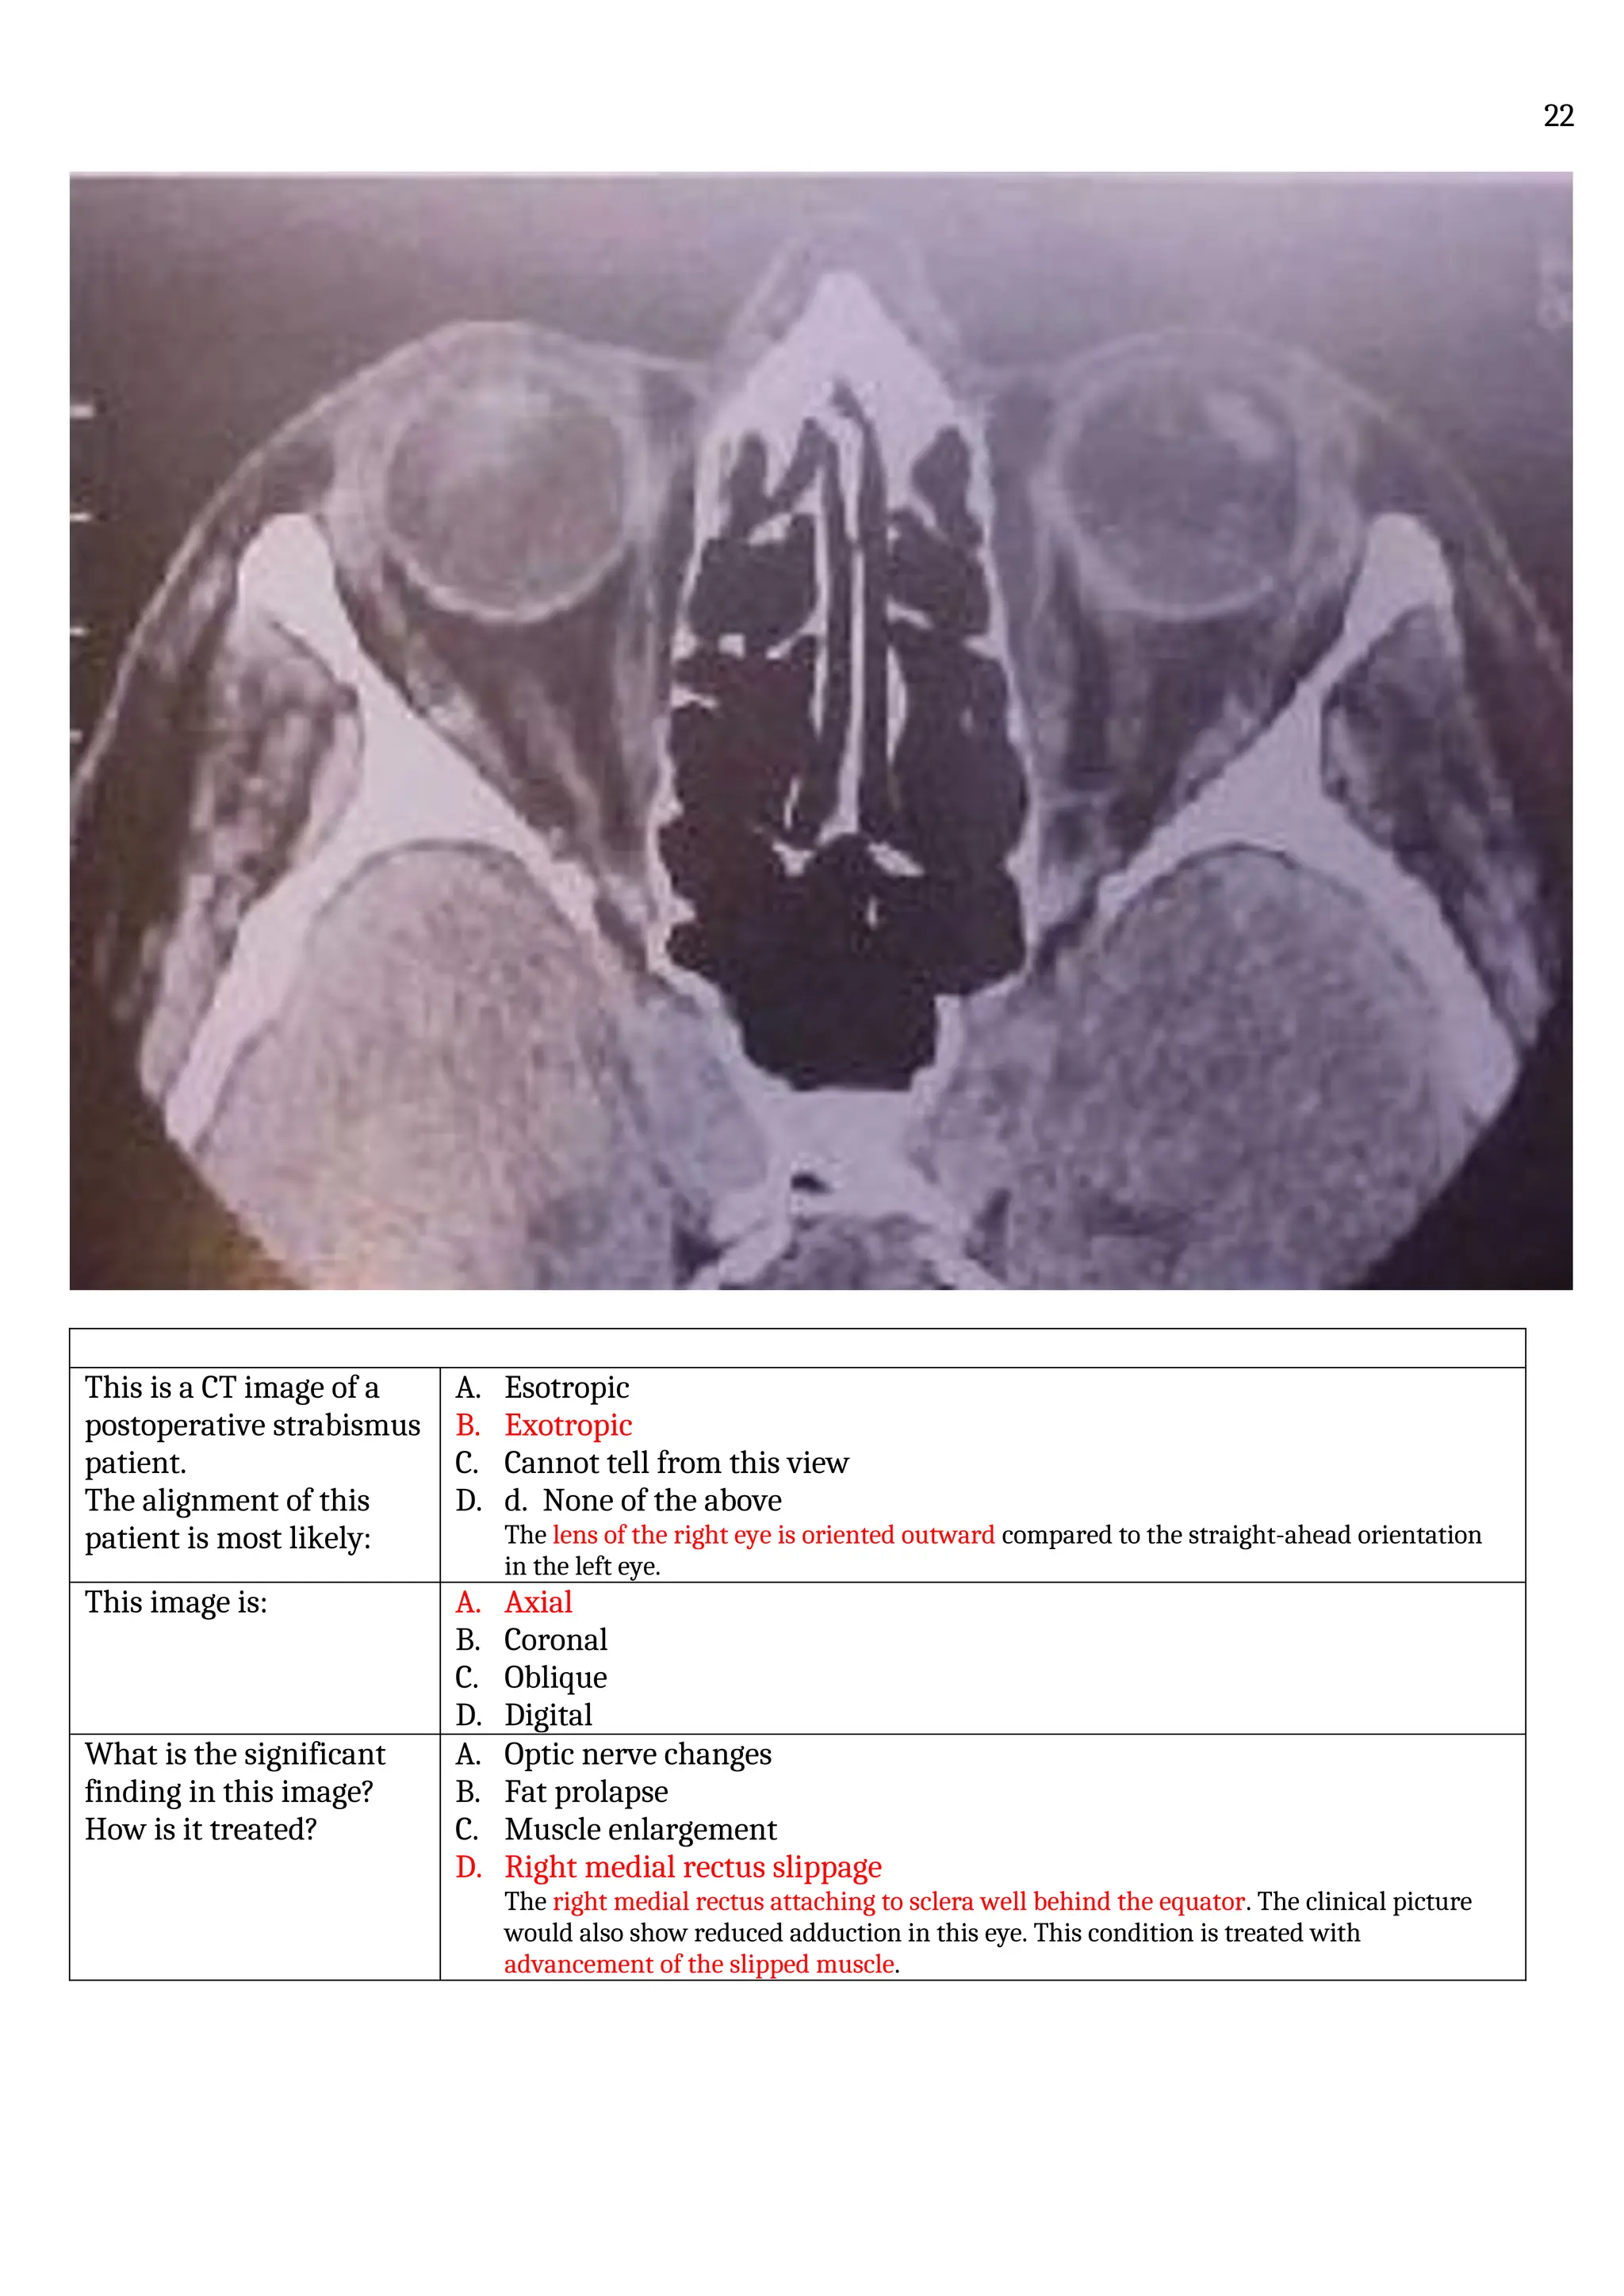

History:

• A 78 years old lady attended her doctor for a routine eye examination.

• She had not noticed any problems.

Her doctor noticed a visual field defect.

Where are the defects?  Missing visual fields are in the right field of each eye

• What would these

visual field defects be

due to?

• Could the patient

have glaucoma?

Both defects in the right visual field:

 This could be a stroke or other brain lesion

This patient could have glaucoma. BUT:

• Glaucoma defects generally cross the midline or are partly “symmetrical”.

So glaucoma is unlikely.

How do optic nerves

look?

Can you predict the

patient’s condition?

There is no optic disc cupping. Glaucoma is unlikely

A patient with CVA will have healthy optic discs

What other test would

confirm the diagnosis?

CT Scan: shows an area of low density in the occipital lobe, probably an

infarction